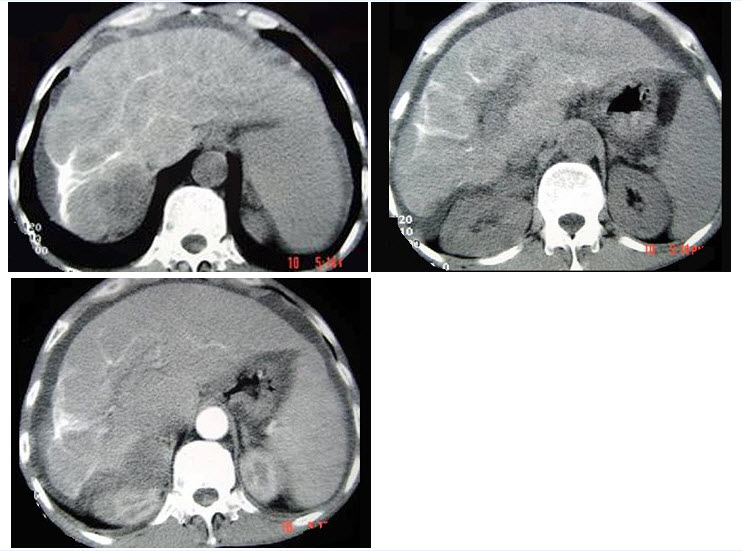

男,63岁,腹胀、双下肢浮肿、乏力、食欲不振,结合图像,最可能的诊断是()

A、酒精性肝硬化

B、血吸虫肝硬化

C、肝炎后肝硬化

D、局限性脂肪肝

E、原发性肝癌

B